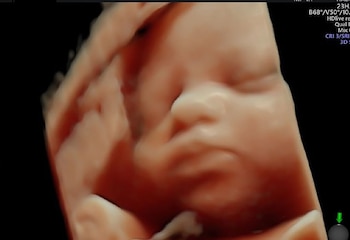

La revolución tecnológica llegó al campo de la ecografía prenatal, presentando la innovadora ecografía en 6D, que permite observaciones detalladas y anticipadas de posibles anomalías en el feto, como malformaciones del corazón y cerebro, lo que facilita un diagnóstico más preciso desde las primeras semanas de gestación.

La Clínica Miraflores en Perú y la Clínica Ripoll en Barcelona encabezan esta avanzada tecnológica con equipos de última generación capaces de brindar imágenes en Súper HD, permitiendo a los futuros padres conocer en detalle y con una claridad sin precedentes el rostro y la anatomía de su bebé aún en el útero.

Estos centros médicos, equipados con ecógrafos GE Voluson E10 BT18 de General Electric, ofrecen una visualización en tiempo real del feto, logrando un nuevo nivel de precisión diagnóstica que abarca desde la detección de condiciones como el labio leporino y la espina bífida hasta anomalías cerebrales y cardiacas.

“Con estos nuevos equipos ya podemos evaluar con minuciosidad órganos complejos... y descartamos malformaciones con mucha anticipación”, señaló Rafael Ascenzo Aparicio, especialista en ecografía fetal de la Clínica Miraflores.

Más allá de su valor diagnóstico, estos avances tecnológicos tienen un profundo impacto emocional en los padres, ya que la transmisión de imágenes y videos directamente a sus teléfonos les permite formar un vínculo único con su bebé antes de su nacimiento. Este aspecto sentimental es reforzado por la posibilidad de visualizar características físicas detalladas, como el rostro del feto, gracias a la tecnología Radiance que otorga una imagen casi transparente de los tejidos.